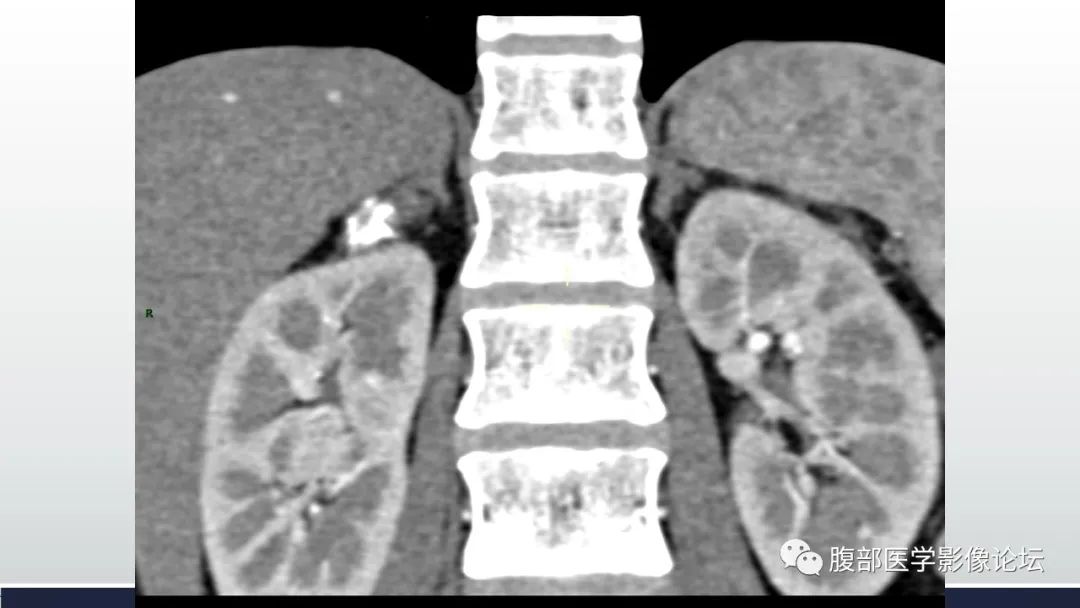

肾上腺平滑肌瘤伴钙化1例CT影像

李广明:右侧肾上腺外侧支结节,环状钙化,其内以囊性为主,尚可见稍高密度灶,增强强化不明显,左侧肾上腺稍增生。考虑1囊肿类,病灶环状钙化,需要优先考虑囊肿病变出血所致,a血肿机化及囊变,一般有外伤病史。b支气管囊肿,影像表现亦符合。2炎症,结核,肾上腺结核一般伴有爱迪生氏综合症,该患者临床没有提示。3肿瘤神经源性,强化偏弱,此种改变不典型。综合考虑肾上腺良性病变,囊肿类首先考虑,陈旧性血肿或支气管囊肿。建议核磁检查,除外肿瘤囊变。 医学百科网 | YxBaike.Com

结果:肾上腺平滑肌瘤 肾上腺平滑肌瘤一般无明显临床症状,多在体检或其他疾病临床诊治中偶然发现,亦呈“偶发瘤”。但是个别患者因肿瘤增大对周围组织压迫而出现腰部疼痛等症状。由于无内分泌功能,因此肾上腺皮髓质分泌功能正常,皮质醇、肾素、血管紧张素、醛固酮均无异常改变。影像表现为肾上腺区圆形或类圆形实质性肿块,质地均匀,部分有钙化,强化不明显,确诊有待病理检查。手术切除为主要治疗方法,术后无复发。

赵德利:适合我的三板斧和原则,第一板,钙化多见于四大类:囊肿,腺瘤,髓质瘤和感染如结核。增强无强化考虑复杂囊肿,强化考虑腺瘤。 医学百科网 | YxBaike.Com

徐钢:环形钙化,里面有轻度强化,静脉期退出,延迟又有强化,不知是不是测量的问题,但是延迟确实看到有强化,我考虑良性病变,倾向感染类,结核?至于临床症状有否,要看确切的临床资料 医学百科网 | YxBaike.Com

定量:环形钙化,中心密度减低为主,见少许密度稍高区,增强扫描未见强化;中年女性,平素健康。

定性:良性。

定病:结核>血肿机化>神经源性肿瘤。

邱勇刚:右肾上腺囊性占位,病灶有一定张力,囊内密度偏高,边缘环形钙化,内部轻度强化,考虑良性病变。疾病谱肾上腺血肿,囊肿,完全囊变的神经鞘瘤,节瘤。本例有张力不符合节瘤,强化不太符合神经鞘瘤。血管瘤太少见,考虑血肿>血管瘤。

医风听雨:右侧肾上腺蛋壳样钙化病灶,内部密度不均,(40到60多),这种表现很少见,分析只能一一排除,肿瘤(包括原发和转移),炎症,囊肿。肿瘤的话考虑良性肿瘤,炎症没有特别适合的病变,囊肿可以边缘钙化,但是这个病灶钙化比较厚,不符合。总结还是考虑良性肿瘤。